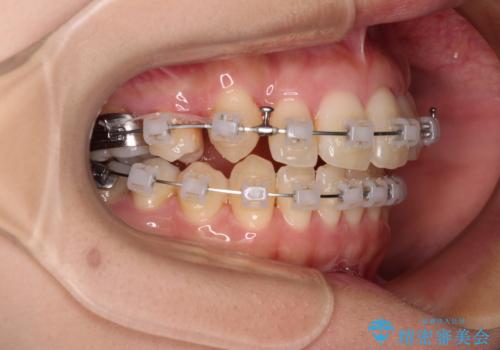

- クリアブラケット

- 1年11ヶ月

下顎歯列の叢生は軽度であることと、口元の突出感が全くなかったことから、八重歯解消のために上顎左右第一小臼歯を抜歯し、ワイヤー装置にて矯正治療を行うこととしました。

八重歯をスムーズに解消するために、補助装置を用いることで速やかに歯列を整えることができました。